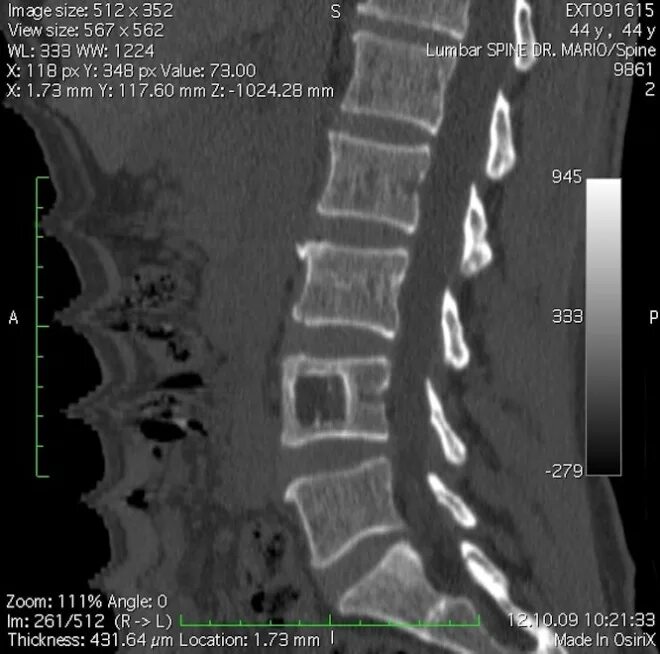

Метастазы в поясничном отделе симптомы